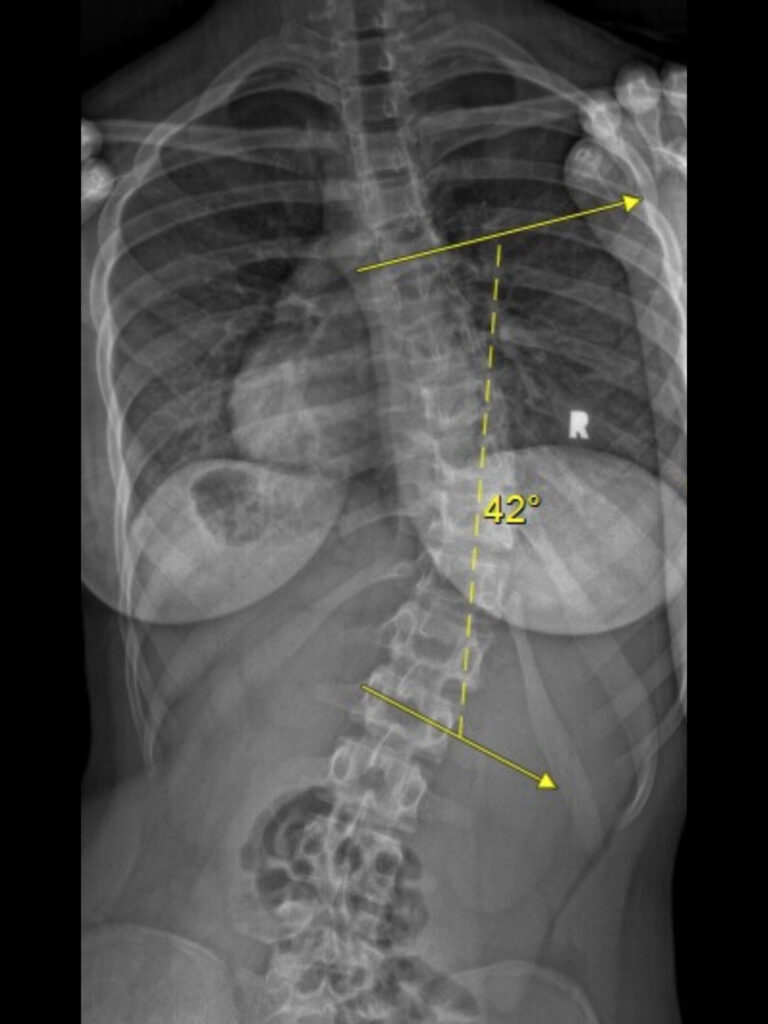

After 3 months of wearing the brace almost 18 hours every day, the out of brace X-ray showed little to no progression with my curve at 38 degrees. This news inspired me to wear the brace 20 hours a day hoping to continue to see my hard work pay off. At my next out of brace X-ray I was feeling confident due to the lack of progression at my previous appointment, though my confidence quickly vanished. My curve was now 42 degrees, even with having worn the brace more. Much of my motivation dissipated after seeing my X-ray results and the shock on my parents faces, I was told I could stop wearing the brace as it clearly wasn’t working. Since stopping wearing the brace I became increasingly aware of the curve in my spine, affecting my body image. I would try to convince myself that no one would notice, even after family or friends saying it was “not noticeable”. It became impossible for me to look in the mirror without noticing my body’s asymmetrical hips, shoulders, and ribs. At this point I had narrowed down my clothing options depending on if I thought people could “see my scoliosis” or not causing my self esteem to decline rapidly.